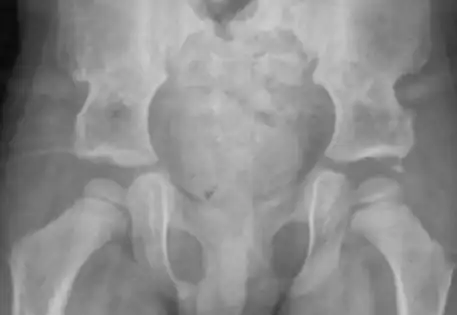

Clinical case B : 2 year old boy presenting with dislocation of both hips

What is the outcome following single-stage hip reconstruction?

Surgical outcomes for late-presenting hip dislocations are typically associated with the age of diagnosis, with less favorable results reported for older children in the literature. Dr. Qureshi employs a single-stage hip reconstruction technique, addressing all deformity elements comprehensively rather than solely focusing on hip relocation. Dr. Qureshi is pleased to showcase successful cases treated with this advanced approach.